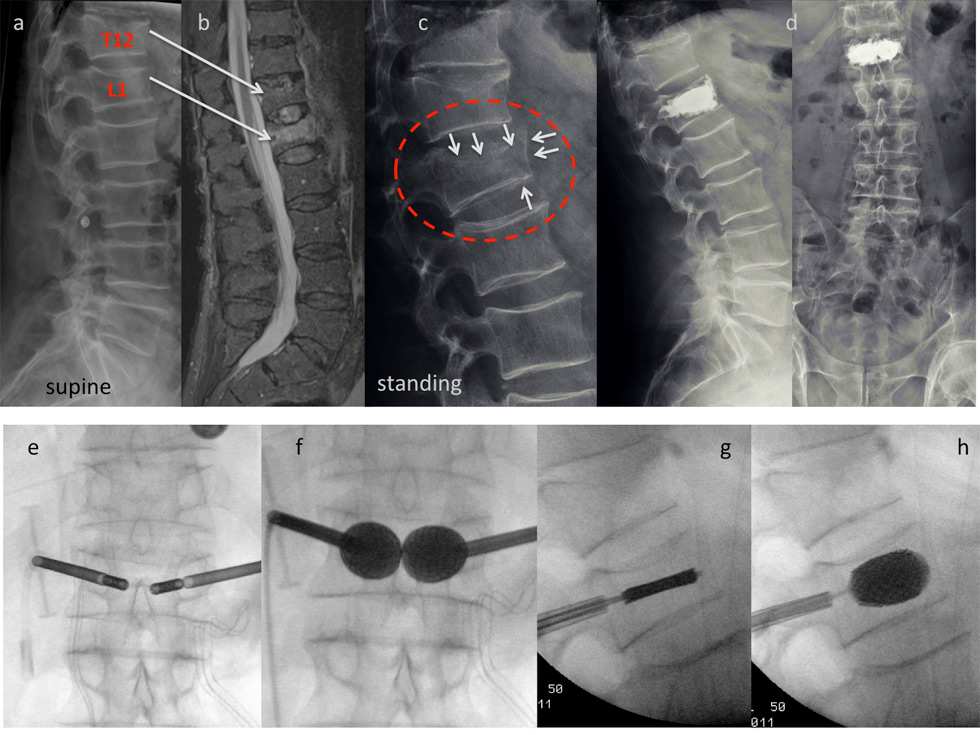

Figure 6

Case report stentoplasty: This 77-year-old male patient is referred to the emergency room after a fall from some 1.5 m. He presents with acute immobilising back pain. The x-ray taken in the supine position depicts fractures of T12 and L1 (a). The MRI scan discloses a fresh fracture of L1, whereas T12 appears old (b). The fracture was considered simple and conservative treatment was initiated with in- hospital physiotherapy and pain medication. After 3 days a standing X-ray was performed which shows a much more complex lesion in comparison to the initial pictures (white arrows): There is a split fracture with anterior wall displacement, and also the upper endplate has subsided considerably (c). A stentoplasty procedure was performed in local anesthesia, which did provide good height restoration and immediate stabilisation (d). The intraoperative pictures demonstrate complete restoration of the vertebral body’s shape (e-h).